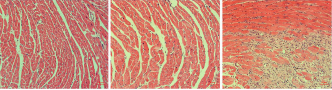

METHODS: Twenty-one male C57BL/6J mice, aged 6-8 weeks, were randomly divided into three groups: the control group, the exercise training group, and the isoproterenol group, with 7 mice in each group. Mice in the exercise training group were subjected to continuous exercise training for 8 weeks to establish a model of exercise-induced cardiac hypertrophy, while mice in the isoproterenol group were injected subcutaneously with isoproterenol for 7 days to establish a model of pathological cardiac hypertrophy. After successful modeling was verified by assessing the heart mass index, heart mass to tibial length ratio, and performing hematoxylin-eosin staining, wheat germ agglutinin staining, and Sirius red staining, the differential protein expression profiles and functional characteristics of the two cardiac hypertrophy models were analyzed using tandem mass tag-based proteomic technology.

RESULTS AND CONCLUSION: (1) Compared with the control group, the heart mass index and heart mass to tibial length ratio were significantly increased in the exercise training group and isoproterenol group (P < 0.001, P < 0.05). Myocardial cells in the isoproterenol group exhibited more severe damage compared with the control group, as evidenced by the disorganized arrangement of cardiomyocytes and extensive inflammatory cell infiltration. (2) The cross-sectional area of myocardial cells was significantly increased in the exercise training group and isoproterenol group compared with the control group (P < 0.05, P < 0.01). The area of myocardial fibrosis was significantly higher in the isoproterenol group compared with the control group (P < 0.01). (3) Proteomic analysis revealed 46 differentially expressed proteins in the exercise training group compared with the control group, 302 differentially expressed proteins in the isoproterenol group compared with the control group, and 340 differentially expressed proteins in the exercise training group compared with the isoproterenol group. Among the differentially expressed proteins in the three comparison groups, two intersection proteins were identified as peroxisomal acyl-coenzyme A oxidase 1 (Acox1) and galectin-3. (4) Gene Ontology and Kyoto Encyclopedia of Genes and Genomes enrichment analysis suggested that exercise might induce physiological cardiac hypertrophy by upregulating Acox1 to promote fatty acid metabolism. In contrast, isoproterenol might induce pathological cardiac hypertrophy by downregulating Acox1, potentially leading to peroxisome dysregulation and lipotoxicity. These results suggest that Acox1 and galectin-3 proteins may serve as potential intervention targets for the treatment or prevention of pathological cardiac hypertrophy.